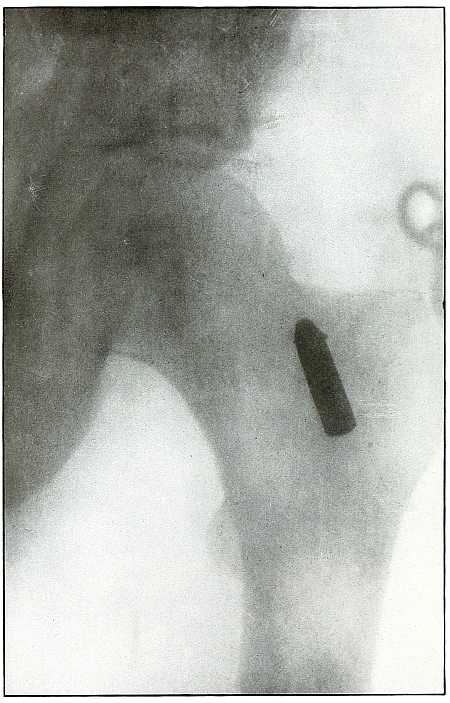

Plate 48.

_

[Pg 107]

Rifle—Plate 48.

LOWER EXTREMITY.

Gunshot Wound of the Thigh,

with Lodgment of the Bullet.

Wound of entrance, outer aspect of the thigh at the junction of the upper and middle thirds.

The slight penetration without bone injury and with slight deformity of the nose of the bullet indicates that the wound was caused by a ricochet shot at extreme range, after its energy was almost spent.

With the posterior aspect of the thigh next to the plate, the dense shadow and the nearly normal size of its outline indicate that the bullet was in the same relative position and that it lay posterior to the neck of the femur.

As such wounds are rarely infected, the treatment is conservative, and a search for the missile is only justified by serious infection, pain, or impaired function. [Pg 108]